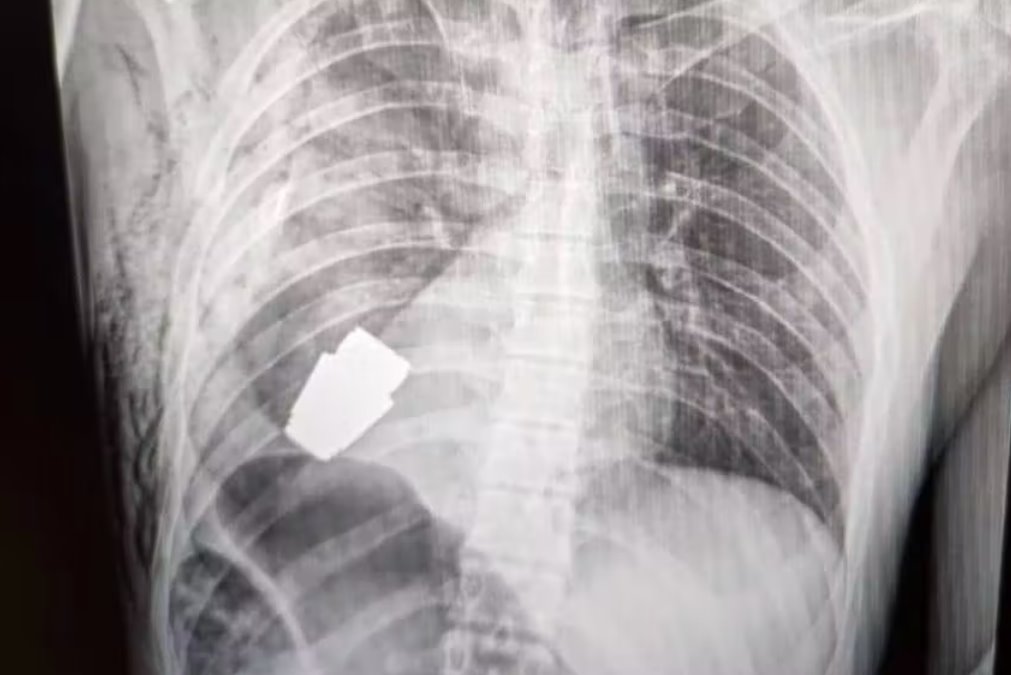

軍方發(fā)布了一張位于一個人軀干內(nèi)的手榴彈的X光片和一張Verba在手術(shù)后手持血淋淋的手榴彈的照片。

該裝置是一枚VOG手榴彈,是一種四厘米長的炸彈,設(shè)計(jì)用于從榴彈發(fā)射器發(fā)射并在地面上爆炸。